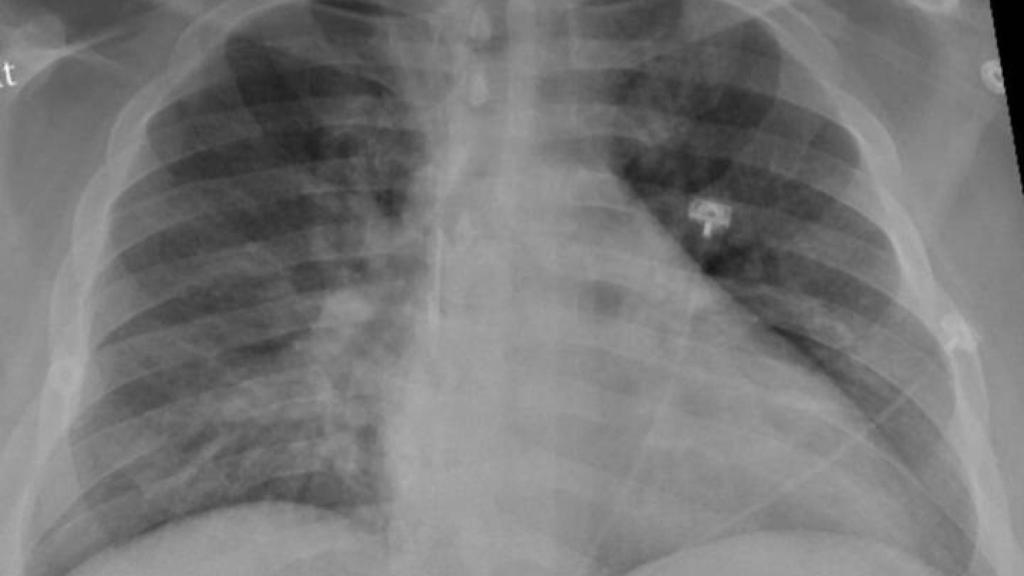

El tejido pulmonar de pacientes que sufrieron el COVID-19 de forma grave muestra una buena recuperación en la mayoría de los casos. Así lo reveló un estudio realizado por el centro médico universitario de Radboud que ahora se ha publicado en la revista 'Clinical Infectious Diseases'.

El estudio, dirigido por el neumólogo Bram van den Borst, incluyó a 124 pacientes que se habían recuperado de infecciones agudas por COVID-19. Visitaron la clínica de cuidados posteriores corona del centro médico de la universidad de Radboud, en Países Bajos. Los pacientes fueron examinados por tomografía computarizada y una prueba de función pulmonar, entre otros análisis.

Después de tres meses, los investigadores hicieron un balance, que reveló que el tejido pulmonar de los pacientes se estaba recuperando bien. El daño residual en el tejido pulmonar fue generalmente limitado y se observa con mayor frecuencia en pacientes que fueron tratados en la UCI.

El investigador principal y neumólogo Bram van den Borst explica: "Los patrones que vemos en estos pacientes muestran similitudes con la recuperación después de una neumonía aguda o síndrome de dificultad respiratoria aguda (SDRA), en el que se acumula líquido en los pulmones durante mucho tiempo. Es alentador ver que los pulmones después de las infecciones por COVID-19 exhiben este nivel de recuperación", apostilla.